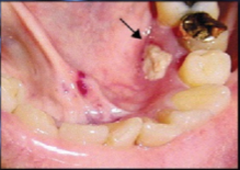

periapical granuloma

-asymptomatic, tooth sensitive to percussion, slight extrusion of tooth -radiographically: slight thickening PDL and periodontal radiolucency CHRONIC